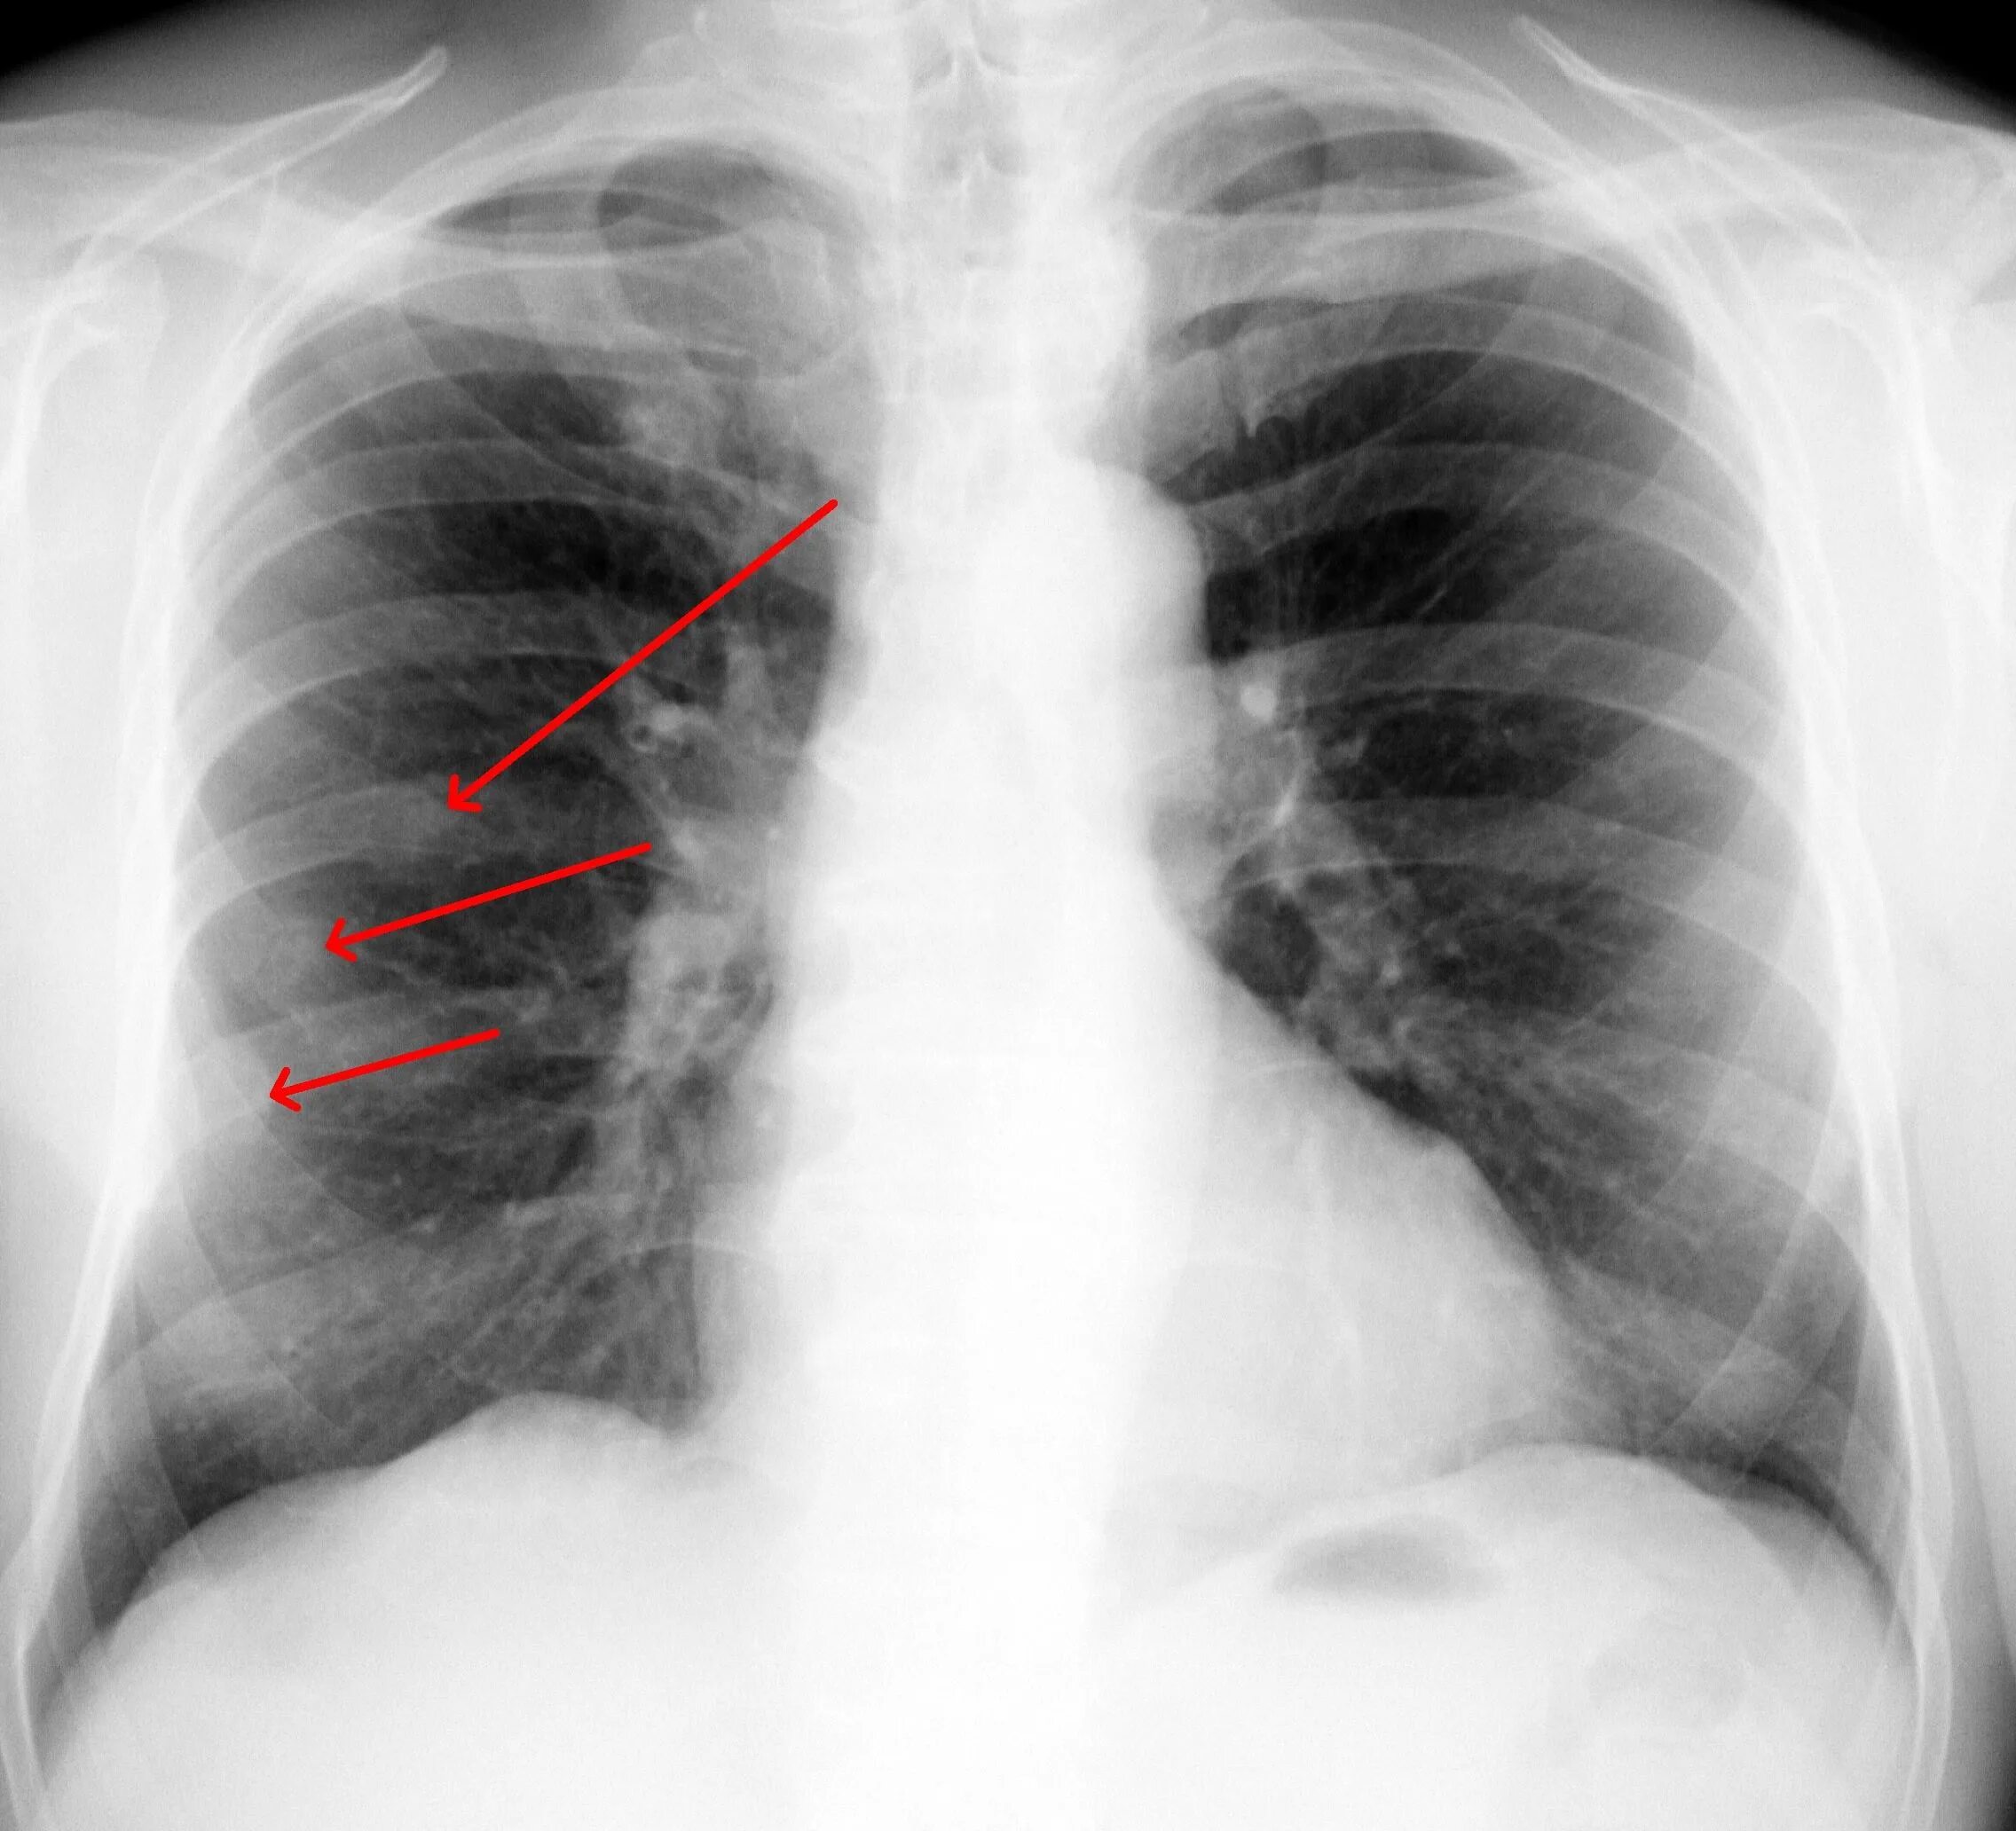

Перелом 5 6 7 ребер